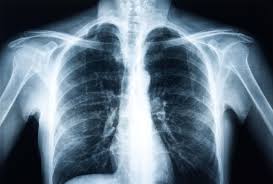

Chest X-Ray

Your lungs tell a story. Let a chest X-ray reveal it.